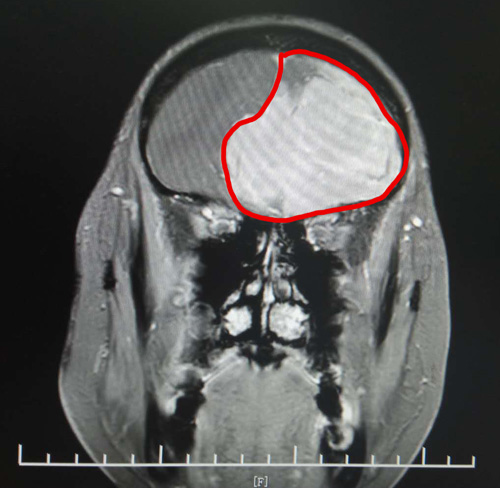

頭顱MRI增強(qiáng)顯示,丁阿姨的前顱窩有巨大的團(tuán)塊狀異常信號(hào)。腫瘤大小約為6.9×5.6×5.4厘米,其大小與鴨蛋接近。

頭顱MRI影像清晰顯示了巨大的腦膜瘤

由于巨大腫瘤壓迫患者不少重要的神經(jīng),腫瘤已將周?chē)DX組織結(jié)構(gòu)和主要腦供血?jiǎng)用}擠壓得嚴(yán)重變形,手術(shù)難度很大。

在將大出血風(fēng)險(xiǎn)顯著降低后,沈建康教授親自主刀,為丁阿姨進(jìn)行了腫瘤切除。手術(shù)中可以清楚看到,這個(gè)體積巨大的腫瘤已跨過(guò)中線,侵入患者的右側(cè)額葉顱底。沈教授的手術(shù)刀一次次精準(zhǔn)避開(kāi)細(xì)小的血管和神經(jīng),將腫瘤分塊全部切除。歷時(shí)近4小時(shí),手術(shù)取得了圓滿成功。術(shù)后,丁阿姨很快恢復(fù)清醒,在醫(yī)護(hù)人員和家人的精心照料下,身體狀況恢復(fù)較好。